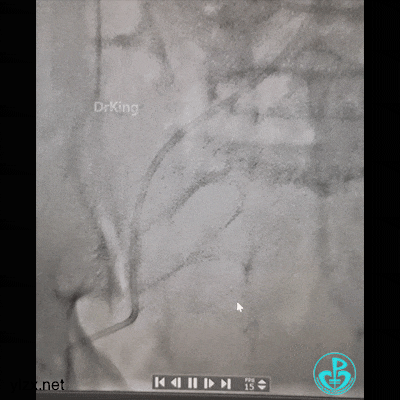

打折处通了,换软头端(直头端不敢出GC)。

管子头段直啦。

拉出来了。

股A造影正常,撤台,安返CCU。